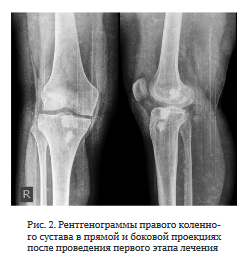

Диагноз: Хронический посттравматический остеомиелит правого бедра и большеберцовой кости. Артрит правого коленного сустава. Состояние после протезирования ПКС правого коленного сустава (рис. 1).

Из анамнеза заболевания: 2010 г. — травма правого коленного сустава, повреждение ПКС, артроскопическое протезирование ПКС. Июнь 2016 г. — повторная травма, лечебно-диагностическая артроскопия с резекцией медиального мениска. Июнь 2021 г. — травма правого коленного сустава с повреждением трансплантата ПКС.

Июль 2021 г. — повторная резекция медиального мениска артроскопически и ревизионное протезирование ПКС, в послеоперационном периоде — гнойный артрит.

Август 2021 г. — дренирование коленного сустава.